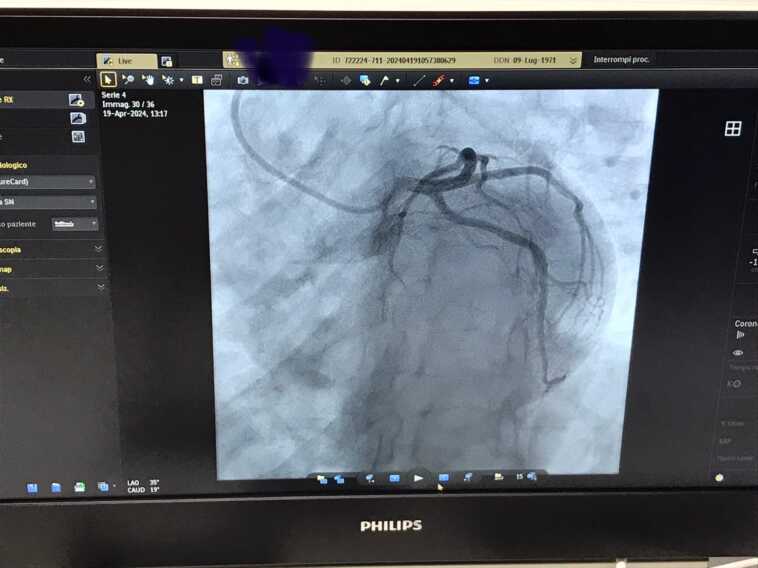

Torna operativa, nell’ospedale Perrino di Brindisi, la sala per l’emodinamica del reparto di Cardiologia a seguito della realizzazione di lavori edili e dell’installazione dell’angiografo Philips Azurion.